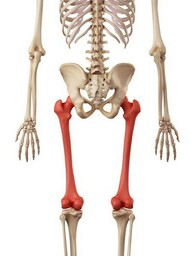

The pelvis protects your intestines. The large leg bones are called the femur, the tibia and the fibia. They are joined together by the knee joint, which is protected by a bone called the patella.